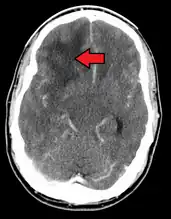

GBM in the frontal right lobe as seen on CT scan -